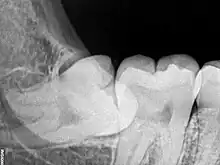

Problèmes liés à son éruption

Souvent elle est formée, mais ne peut faire totalement son éruption en bouche. Cela est dû :

- soit à un manque de place. La dent de sagesse se situe souvent au niveau de la branche montante de la mandibule, elle est donc partiellement ou totalement bloquée ;

- soit car son axe d'éruption n'est pas correct. Les dents de sagesse ont souvent des axes d'éruption fantaisistes, et des formes très variables.

Lorsque la dent bute sur le collet de la deuxième molaire, elle est bloquée dans son extériorisation. On dit qu'elle est « enclavée ».

La dent est dite « incluse » lorsqu'elle est entièrement recouverte par l'os et la gencive, au niveau de la face postérieure de la racine de la deuxième molaire.

Entre 15 et 25 % des dents de sagesse mandibulaires sont incluses ou enclavées[13].